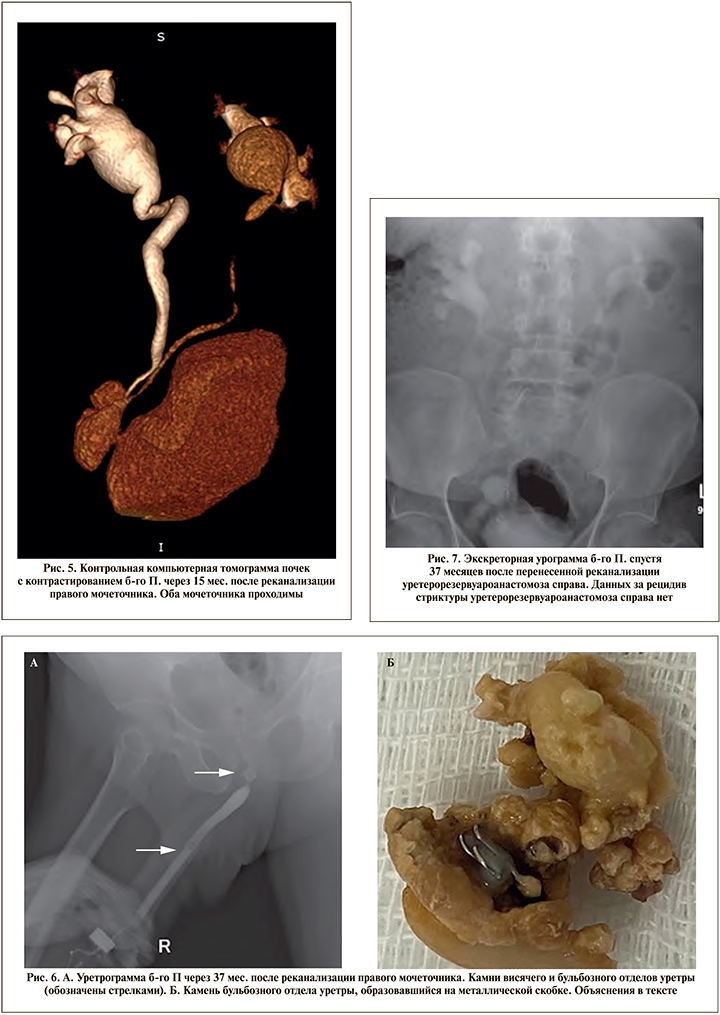

Оперативное вмешательство выполнено под эндотрахеальным наркозом в условиях рентген-операционной в литотомическом положении пациента. Первым этапом произведено контрастирование чашечно-лоханочной системы с последующим антеградным проведением двух струн-проводников (рабочей и страховой) до уровня облитерации мочеточника. В дальнейшем по струне-проводнику к области облитерации антеградно доставлен катетер с встроенным оптоволоконным световодом размером 7 Fr (рис. 1). Вторым этапом произведена трансуретральная резервуароскопия гибким цисто- и резектоскопом. Визуализировать устье правого мочеточника не представилось возможным, в связи с чем резервуароскопия выполнена с выключенным осветителем и параллельной антеградной подсветкой ранее проведенного в мочеточник катетера со встроенным световодом (рис. 2). Визуализировано место предполагаемого устья правого мочеточника, рассеченного путем монополярной электрохирургии «на свет» («cut to the light»). Визуализирован просвет мочеточника с находящимися внутри него антеградно заведенными струнойпроводником и светящимся катетером (рис. 3). Струна-проводник выведена через уретру наружу, и выполнено бужирование мочеточника при помощи мочеточниковых бужей 10–16 Fr. Просвет мочеточника сформирован адекватно. Протяженность облитерации составила не более 1 см. С целью шинирования мочеточника в правую почку установлено два внутренних стента диаметром 6 Fr (рис. 4) сроком на 6 мес., после удаления которых нарушения оттока мочи из почек зафиксировано не было. По данным контрольной компьютерной томографии с контрастированием, выполненной спустя 1 год и 3 мес. после удаления внутренних стентов, мочеточники проходимы, признаков рецидивирования стриктуры правого мочеточника выявлено не было (рис. 5).

При дальнейшем наблюдении через 3 года после выполненной реканализации уретерорезервуароанастомоза в отсутствие клинических проявлений со стороны почек (креатинин – 136 мкмоль/л, мочевина – 7,4 ммоль/л) у больного развилась острая задержка мочеиспускания и диагностированы камни уретры, которые, по-видимому, образовались на отторгнувшейся металлической скобке от сшивающего аппарата, использованного для формирования кишечного резервуара в 2017 г. Пациенту выполнена уретрорезервуароскопия, при которой в висячем отделе уретры выявлен конкремент размером 1 см и в бульбозном отделе размером до 2 см выполнена тулиевая волоконная уретролитотрипсия, литоэкстракция (рис. 6). Также пациенту выполнена уретероскопия ригидным уретеропиелоском 8 Fr, при которой проходимость неоустья оценена как адекватная. Данных за рецидив онкопроцесса выявлено не было. При контрольном обследовании данных за рецидив сужения уретерорезервуароанастомоза не получено (рис. 7).